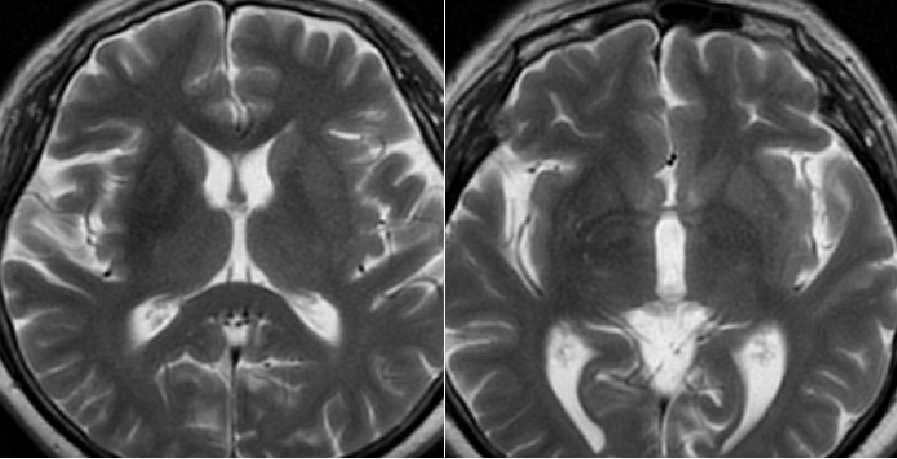

3 天后行 MRI 检查,图像如下:

T1WI 示病灶呈高信号,T2WI 呈低信号,DWI 信号不高,病灶边界清晰,无占位效应及周围水肿,内囊未累及。

影像表现为对侧纹状体(主要为壳核)的异常,CT 上表现为高密度,CT 值约 40-50 HU。T1WI 高信号为该病最主要的影像学特点,T2WI 信号表现各异,多呈低信号,少数呈高或混杂信号,不具有特征性。增强后病灶无强化。病灶边界清晰,无明显水肿及占位效应,不累及内囊。但也有部分病例无任何影像学改变。T1WI 高信号一般持续数月到数年不等,随着病情的好转可减弱甚至消失。

女,58 岁,右侧肢体持续性不自主扭动,既往糖尿病史 20 年,测血糖为 12.17 mmol/L,HbA1c 为 14.5%。CT 示左侧豆状核高密度,边界清晰。T1WI 示病灶呈高信号,T2WI 呈低信号,边界清晰,无占位效应及周围水肿,未累及内囊,增强后未见强化。

女,58 岁,非酮症高血糖性偏侧舞蹈病。CT 示右侧尾状核头及豆状核弥漫性高密度。MRI T1WI 示病灶呈高信号,T2WI 呈低信号,边界清晰。病理切片示右侧基底节出血。